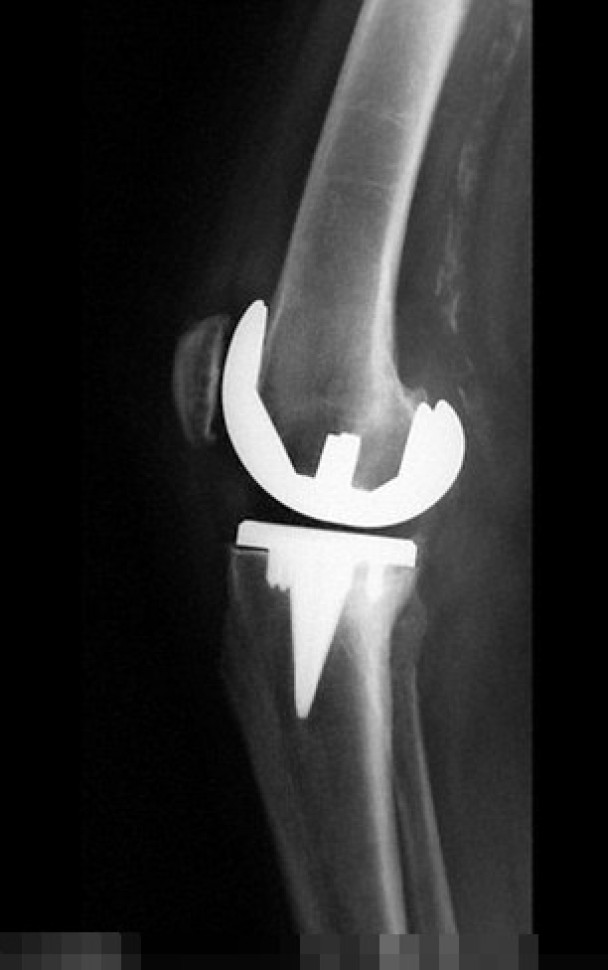

(神秘的地球报道)美国一名65岁妇人5年前因为骨关节炎把膝盖骨换掉,半年前她的右腿和膝盖骨开始疼痛,医生建议她接受针灸纾缓痛楚。惟妇人的膝痛愈来愈严重,膝盖更肿起来,身体又发冷。她立即前往急症室,医生抽取其膝盖关节内的液体化验,结果发现其膝盖骨受一种名为“戈登氏链球菌”(Streptococcus gordonii)的口腔细菌感染,而原因竟然与她使用牙线有关。

有关病例刊登于《英国医学期刊病例报告》(BMJ Case Reports),负责撰写报告的医生指,该名妇人因为用牙线不当令牙肉流血,以致其口腔内滋生“戈登氏链球菌”,细菌之后随血液流到其膝盖,令其假膝盖骨关节亦受感染。医生其后动手术,为妇人清洗膝盖骨上的细菌,并处方抗生素治理,妇人现时正康复。医生又指这是北美首个病例,在此之前医学文献只有1宗同类个案记载。